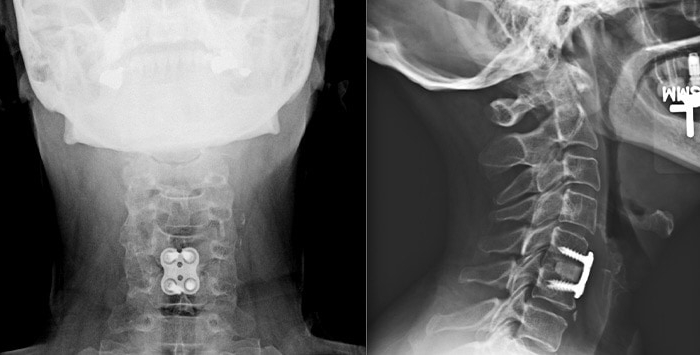

ACDF – Anterior Cervical Discectomy and Fusion

ACDF is one of the most commonly performed spine surgeries. It is a surgical procedure done from the front of the neck (hence, anterior), during which the surgeon removes the abnormal disc (discectomy) and fuses the bones using a spacer, plate, and screws.